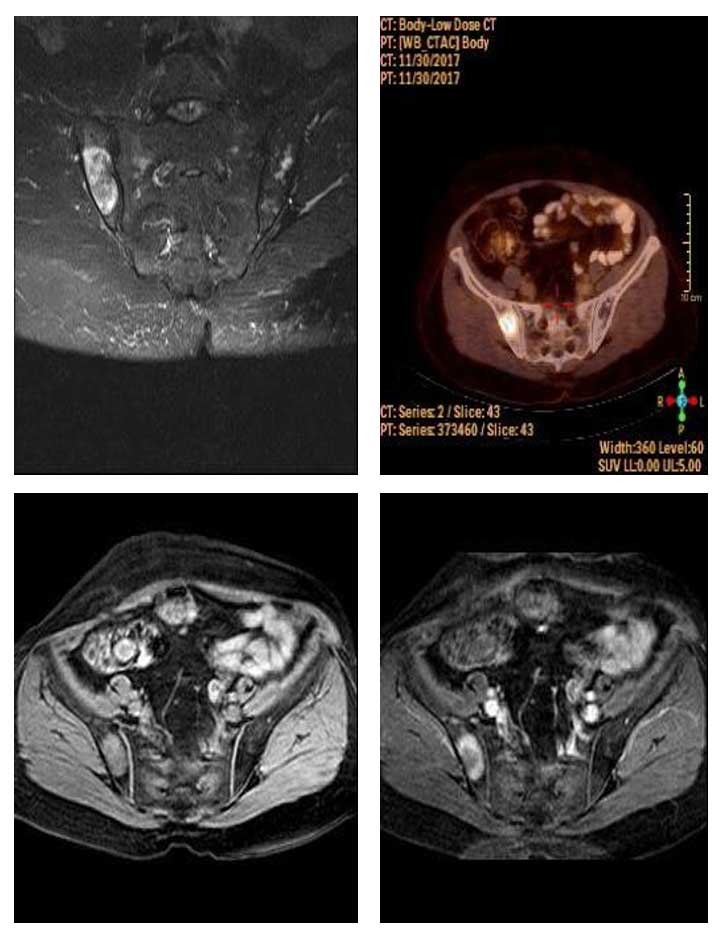

Ameliyat Öncesi: MR’da iliak kanat posterior yerleşimli kontrast tutan heterojen kitle, PET-CT’de yoğun tutulum görülmekte.